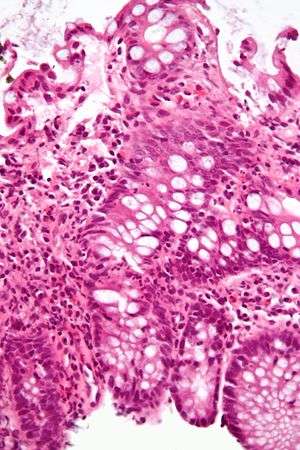

| A micrograph demonstrating cryptitis, a microscopic correlate of colitis. H&E stain. | |

An important investigation in the assessment of colitis is biopsy. A very small piece of tissue (usually about 2mm) is removed from the bowel mucosa during endoscopy and examined under the microscope by a histopathologist. It can provide important information regarding the etiology of the disease and the extent of bowel damage.